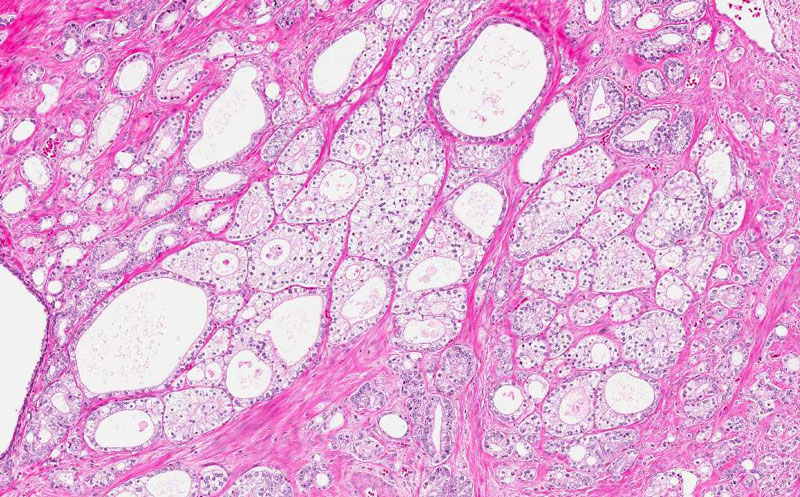

Area 6: This are residual prostatic glands with dilatation and atrophic changes of the epithelium.

Hematoxylin & eosin

• Residual prostatic glands with dilatation and atrophy of epithelium are also present (Area 4).